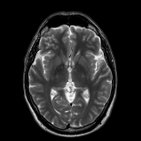

Cerebro (RM)

Una de las secuencias más importantes para la obtención de imágenes del cerebro es la secuencia potenciada en T2. En esta las imágenes del líquido cefalorraquídeo (LCR) -o cualquier tipo de líquido transparente- muestran una hiperintensidad marcada (color blanco), y permite una buena diferenciación entre la sustancia gris y blanca del cerebro.

Las siguientes imágenes muestran algunas de las estructuras que son identificables en la RM potenciada en T2.